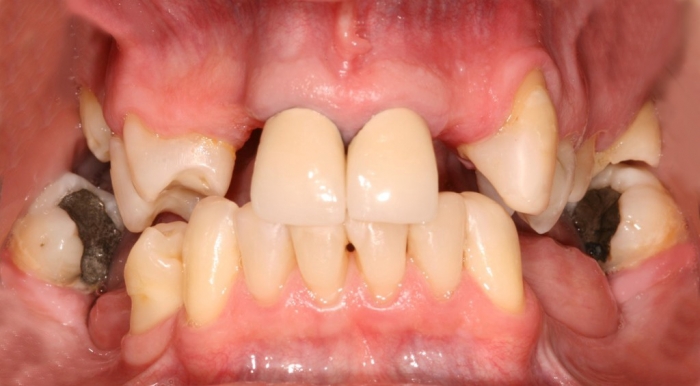

Imagem inicial em 2009 - Clínica Cliniface

Imagem inicial em 2009